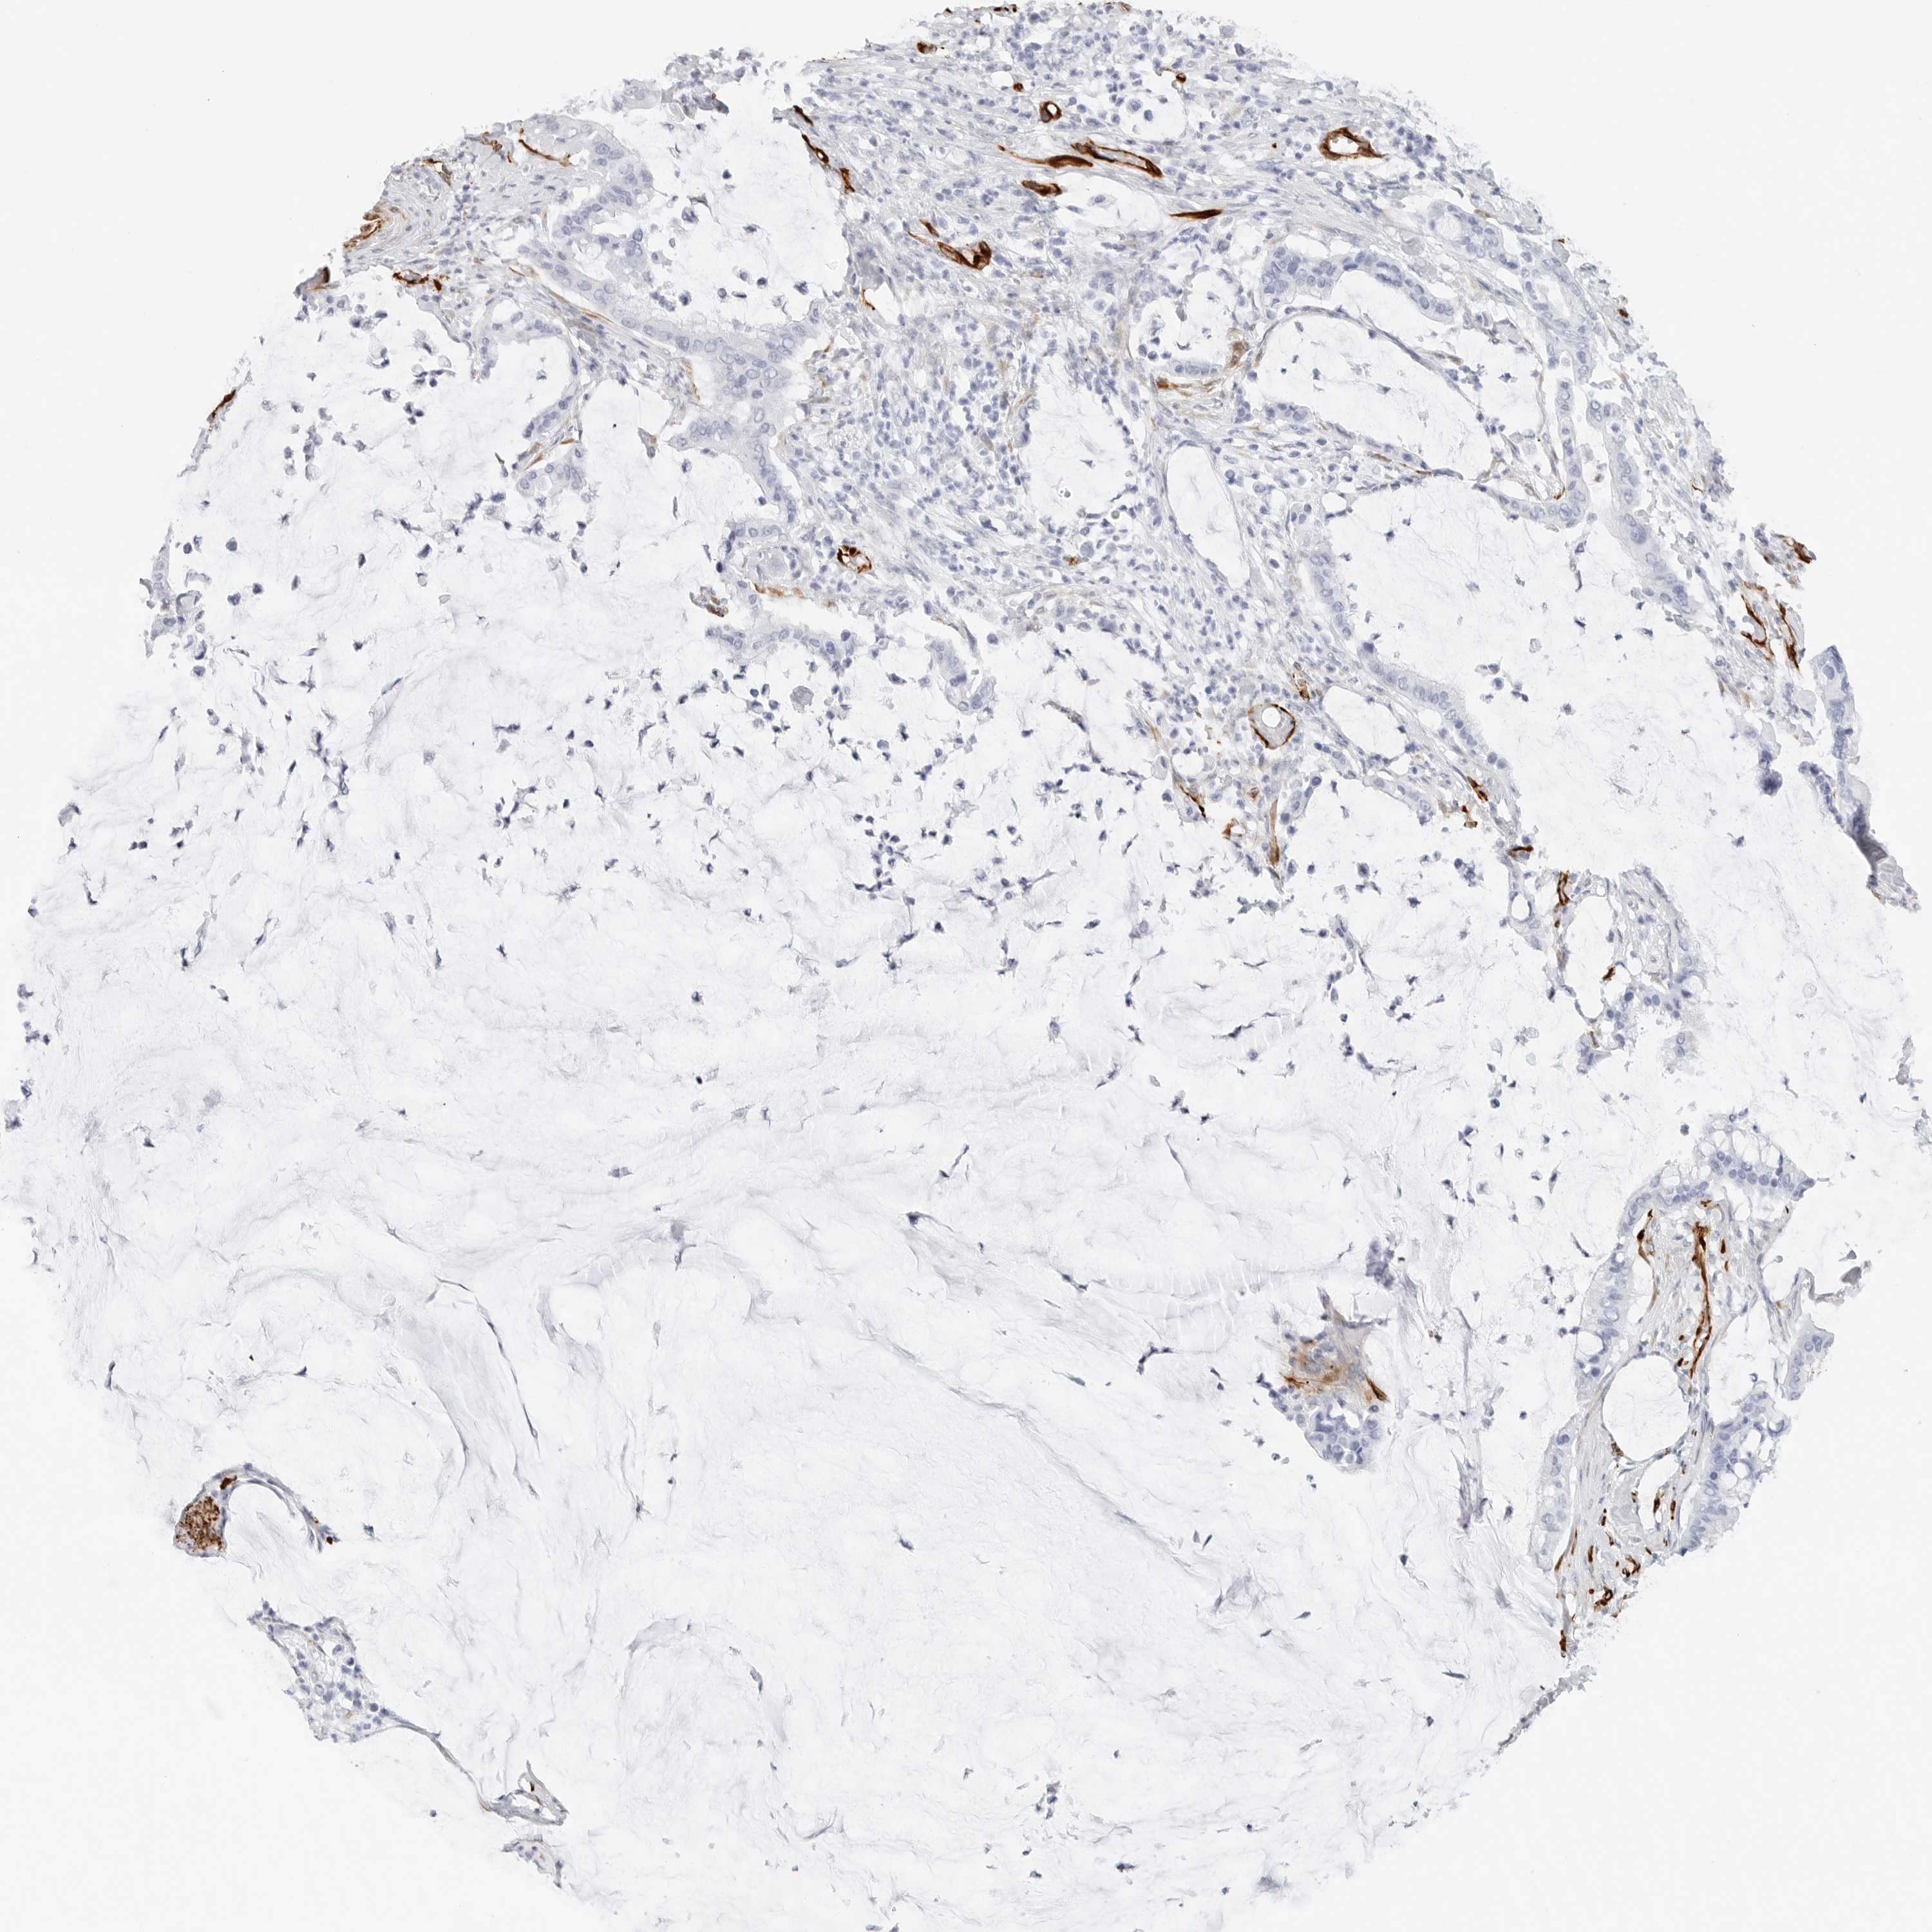

PANCREATIC CANCER - Protein expressioni

A mouse-over function shows sample information and annotation data. Click on an image to view it in a full screen mode. Samples can be filtered based on level of antibody staining by selecting one or several of the following categories: high, medium, low and not detected. The assay and annotation is described here.

Note that samples used for immunohistochemistry by the Human Protein Atlas do not correspond to samples in the TCGA dataset.

Antibody stainingi

Antibody staining in the annotated cell types in the current human tissue is reported as not detected, low, medium, or high, based on conventional immunohistochemistry profiling in selected tissues. This score is based on the combination of the staining intensity and fraction of stained cells.

Each image is clickable and will lead to virtual microscopy that enables deeper exploration of all samples and also displays staining intensity scores, fraction scores and subcellular localization as well as patient and tissue information for each sample.

Antibody HPA007007

Antibody HPA026111

Antibody CAB005889

Antibody CAB058692

Staining

High

Medium

Low

Not detected

Intensity

Strong

Moderate

Weak

Negative

Quantity

>75%

75%-25%

<25%

None

Location

Nuclear

Cytoplasmic/membranous

Cytoplasmic/membranous,nuclear

Adenocarcinoma, NOS

Adenocarcinoma, metastatic, NOS